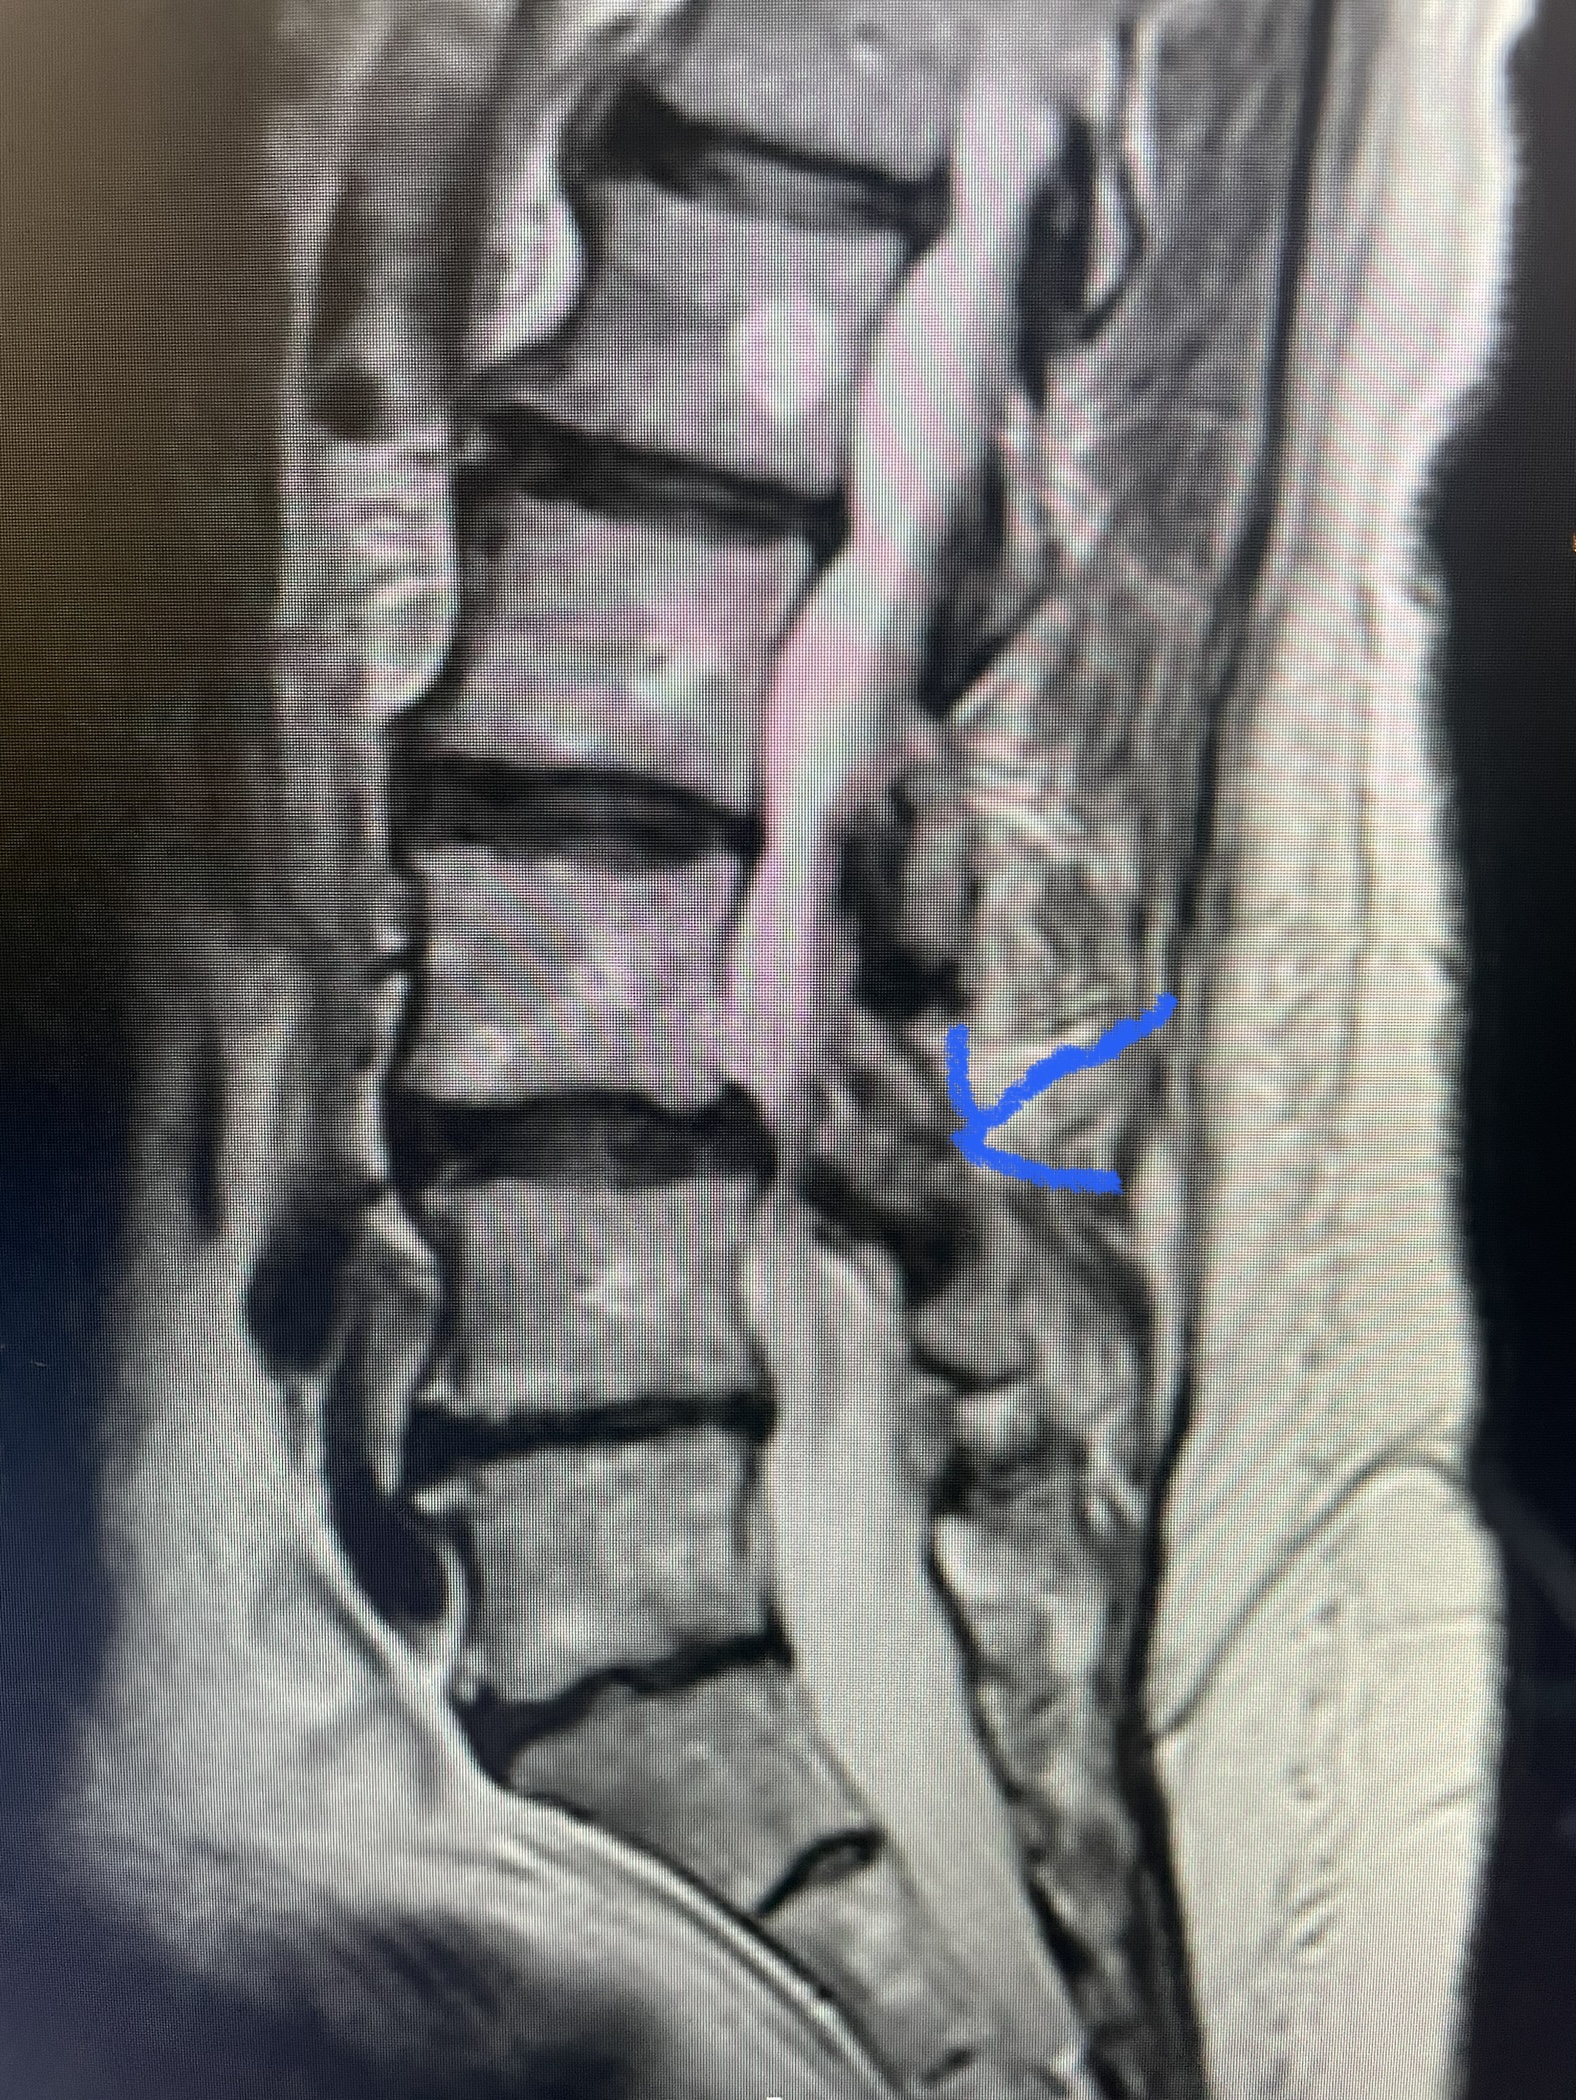

(Fig. 2) T2-weighted lumbar MRI demonstrating severe lumbar stenosis (red markers) and a grade 1 spondylolisthesis at L5-S1 (blue arrow)

This 59 year-old female had severe bilateral leg pain and numbness over a 6-month period. The patient had failed conservative treatment with physical therapy, chiropractic care, and medications. MRI revealed that she had severe lumbar stenosis with a grade 1 spondylolisthesis or “slipped disc” at L5-S1 (Fig. 2). In addition, she had previously undergone both front and back surgery for severe cervical stenosis where her posterior hardware had failed because of her severe osteoporosis requiring us to remove the posterior hardware. This required her to have an anterior or front operation which allowed better fixation to her spine because of the load-sharing nature of the interbody grafts in addition to her anterior cervical plate (Fig. 3).